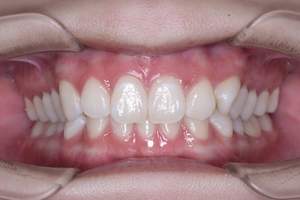

歯石除去、着色除去

治療前

治療後

| 年齢 | 25歳・女性 |

| 主訴 | 主訴:歯石除去、着色除去 治療部位:全顎 |

| 治療内容 | 初診検査・歯石除去・PMTC |

| 治療期間 | 60分 |

| 費用 | 合計約10,500円 初診検査約3,000〜4,000円 歯石除去約1,000円 PMTC5,500円(自費診療) (2024年6月現在) (歯の本数や検査内容で料金が変動します。) |

| リスク・副作用 | ・歯ぐきの炎症がある場合は歯石除去中に出血を伴う可能性があります。 ・処置後、知覚過敏が起こる可能性があります。 ・歯ぐきの炎症が治ると、歯ぐきが引き締まる為歯が長くなったと感じる事があります。 ・PMTCは歯を白くするものではなく着色・バイオフィルムの除去を目的としています。 |

| 治療方針 | 全顎的な歯石除去後、PMTCで着色とバイオフィルムを除去。 |

| 特記事項 | 矯正経験あり ホワイトニング経験あり |

| 担当者所見 | 歯石除去と前歯部の着色除去希望で来院されました。 下顎前歯の歯間部の歯石に対してフロス指導を行いました。 PMTCにより着色がなくなり、歯のトーンアップも感じられたと喜んでくださいました。 |